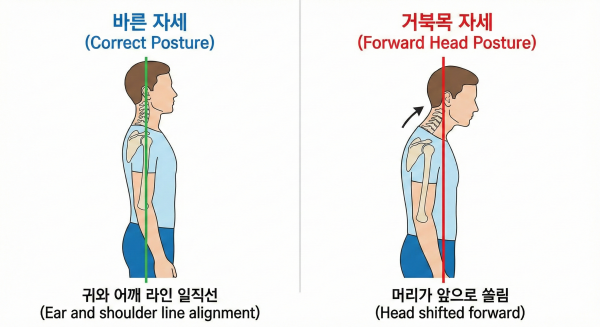

가장 좋은 자세는 귀(외의도)와 어깨, 골반 라인이 일직선 상에 놓이는 것입니다.

본인의 자세가 앞으로 15도 이상 기울어져 있다면 이미 목 건강에 적신호가 켜진 상태입니다.

자가 체크: 고개를 뒤로 제낀 상태에서 통증이 느껴지거나, 한쪽으로 돌렸을 때

어깨와 팔로 찌릿한 통증이 전달된다면 신경 통로가 좁아진 상태일 확률이 높습니다.